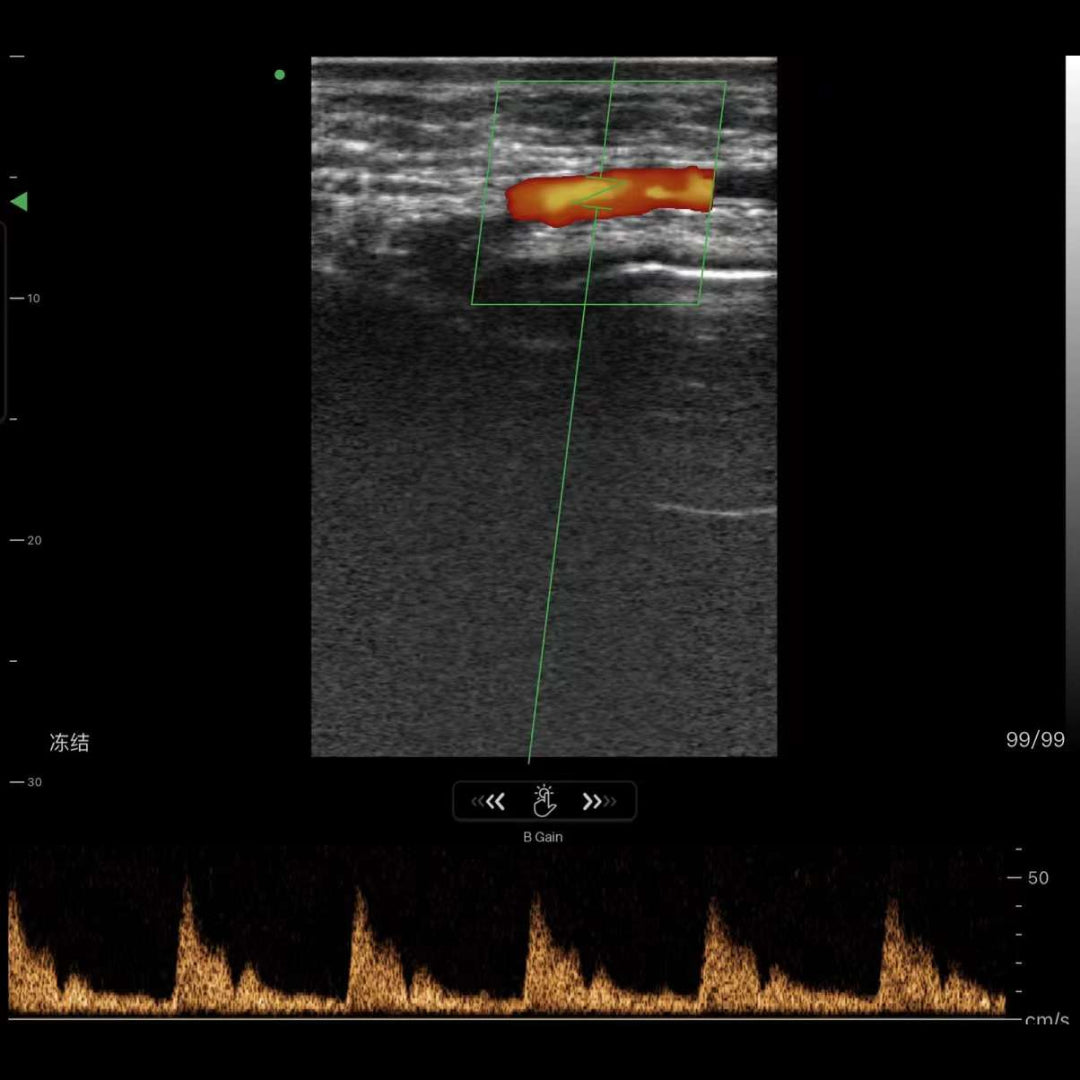

• Guía de inyecciones en cirugía facial.

• Visualización de vasos para cirugía facial reconstructiva/cosmética.

• Medida: B: Longitud, Distancia, Área, Circunferencia, B+M: Tiempo, Distancia, SV, LVID, B+PW: Velocidad, S/D

Imágenes de la vida real

Nuestros dispositivos reproducen una excelente calidad de imagen.